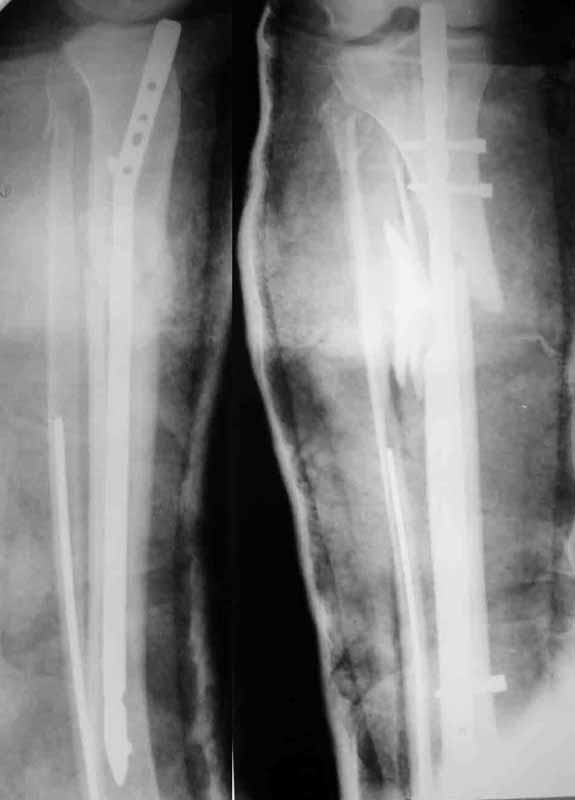

A> Some feedback regarding the case discussed here 6 month ago

I attached images with the nail (Dec 2003) and today with the broken

plate. The fracture site is pretty mobile.

We plan to remove the plate and perform closed nailng.